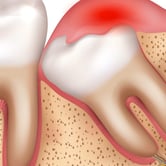

Dientes impactados

Los dientes impactados son dientes que no pueden erupcionar correctamente debido a la falta de espacio o a una obstrucción.

Los pacientes pueden notar que un diente no ha salido, aunque debería haberlo hecho. Esta condición es común con las muelas del juicio y los caninos superiores.

El tratamiento puede incluir la extracción del diente impactado o la creación de espacio para permitir su erupción.